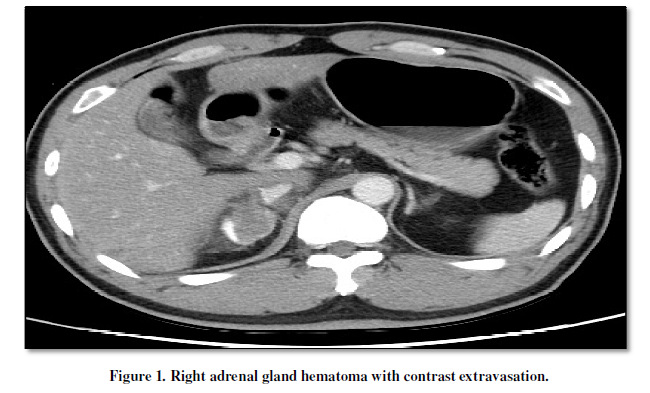

The 44-year-old male with hypertension and diabetic presented in the emergency department with torso pain after motor vehicle crash 30 minutes ago. The pain was located at right upper quadrant, flank, chest and back. Vital signs were stable. The sonography showed ascites over Morison’s pouch. The laboratory data showed GOT of 462 U/L and GPT of 497 U/L. The results of contrast-enhanced computed tomography (CT) were as following: (1) right adrenal gland hematoma with contrast extravasation(Figure 1, Figure 2), (2) liver laceration Grade II (Figure 1),(3) pelvic fracture (Figure 3). He received conservative treatment and discharged smoothly 20 days later.

Traumatic adrenal injury is a relative rare event which is reported in 0.15 to 4% of the blunt abdominal trauma cases[1]. Adrenal trauma is unilateral in 75–90 % of cases and most commonly affects the right adrenal gland [2]. The clinical management of adrenal trauma is usually directed by concomitant injuries, while the adrenal trauma itself is most often managed conservatively [3]. In addition, the most common CT manifestation of adrenal trauma is 2–3-cm oval hematoma [2]. Finally, the adrenal injury is an important indicator of the severity of trauma and associated with increased morbidity and mortality [2], such as in this case.